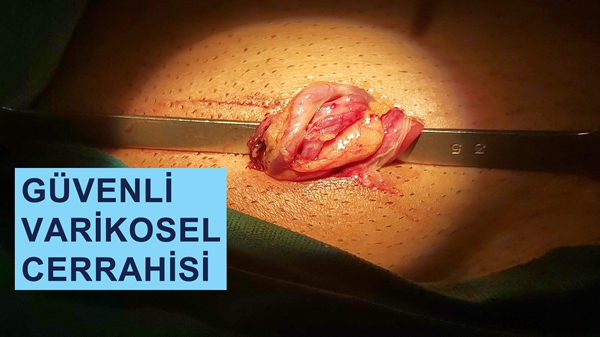

Kısırlık

Cerrahi